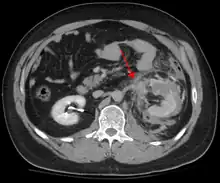

Abdominal CT showing left renal artery injury

Blunt abdominal trauma (BAT) represents 75% of all blunt trauma and is the most common example of this injury.[3] 75% of BAT occurs in motor vehicle crashes,[4] in which rapid deceleration may propel the driver into the steering wheel, dashboard, or seatbelt,[5] causing contusions in less serious cases, or rupture of internal organs from briefly increased intraluminal pressure in the more serious, depending on the force applied. Initially, there may be few indications that serious internal abdominal injury has occurred, making assessment more challenging and requiring a high degree of clinical suspicion.[6]

There are two basic physical mechanisms at play with the potential of injury to intra-abdominal organs: compression and deceleration.[7] The former occurs from a direct blow, such as a punch, or compression against a non-yielding object such as a seat belt or steering column. This force may deform a hollow organ, increasing its intraluminal or internal pressure and possibly lead to rupture.

Deceleration, on the other hand, causes stretching and shearing at the points where mobile contents in the abdomen, like bowel, are anchored. This can cause tearing of the mesentery of the bowel and injury to the blood vessels that travel within the mesentery. Classic examples of these mechanisms are a hepatic tear along the ligamentum teres and injuries to the renal arteries.